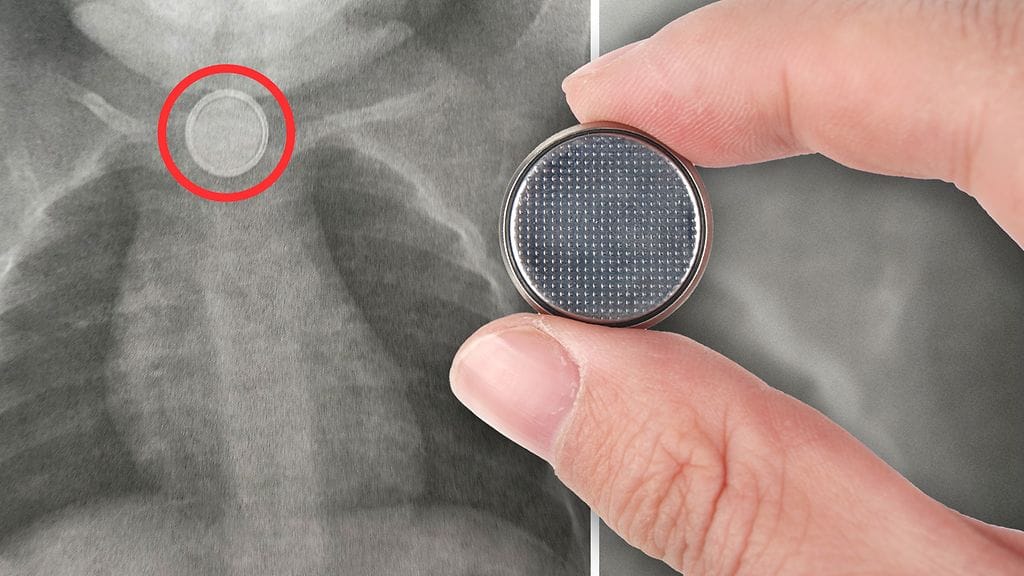

Tapahtumat saivat alkunsa viikko sitten torstaina, kun Valkilan perheen yksivuotias Leo-poika sai käsiinsä kaukosäätimen kolikkopariston.

– Hän kertoi, että säädin oli hetkeä aiemmin ollut pikkuveljen kädessä. Säätimestä puuttui patterin kotelo. Myöskään itse patteria ei löytynyt.

Tässä vaiheessa Hannamari tajusi, että patteri oli Leon nielussa.